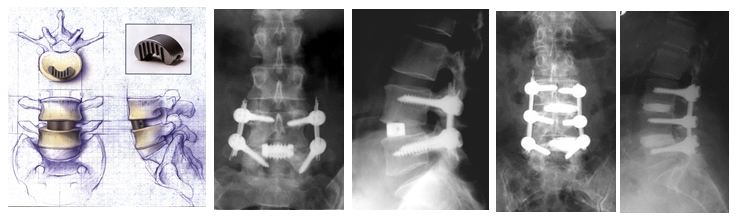

A legszomorúbb az egészben az, hogy megtudtam miért nem akarnak még műteni az orvosok, miért mondják, hogy túl fiatal vagyok. Azért, mert az operáció velejárója, hogy az implantátum csak úgy helyezhető be, ha az izomzatot leválasztják a gerincről mindkét oldalon.

Nyilván ezek az izmok csak hosszabb idő alatt rendszeres gyógytornával regenerálódnak. A legtöbb esetben ez életfogytig tartó gyógytornát jelent. Ha pedig nem sikerül az izomműködést visszaállítani az izomerő gyengülést vagy bénulást vonhat maga után.

Ehhez nagyon jó szakemberre, sőt gyógytornászra lenne szükségem. Az elmondott tapasztalataim alapján arra jutottam, hogy ebben az országban nagyítóval sem találok felelősségteljes terapeutát. Így biztos, hogy Belgiumban nem fognak megműteni, inkább majd otthon.